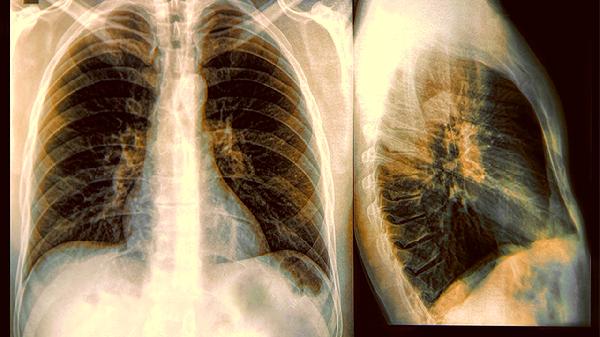

肺部有病,喉咙先知?若喉咙出现4个症状,应及时就医检查!要多加注意

冬季干燥的空气会掩盖很多呼吸道异常,建议在暖气房里放置湿度计,保持50%左右的相对湿度。当这些信号出现时,别急着用润喉糖掩盖症状,及时做低剂量肺部CT检查能发现早期病变。记住,喉咙是呼吸道的守门人,它的每个异常信号都值得认真对待。